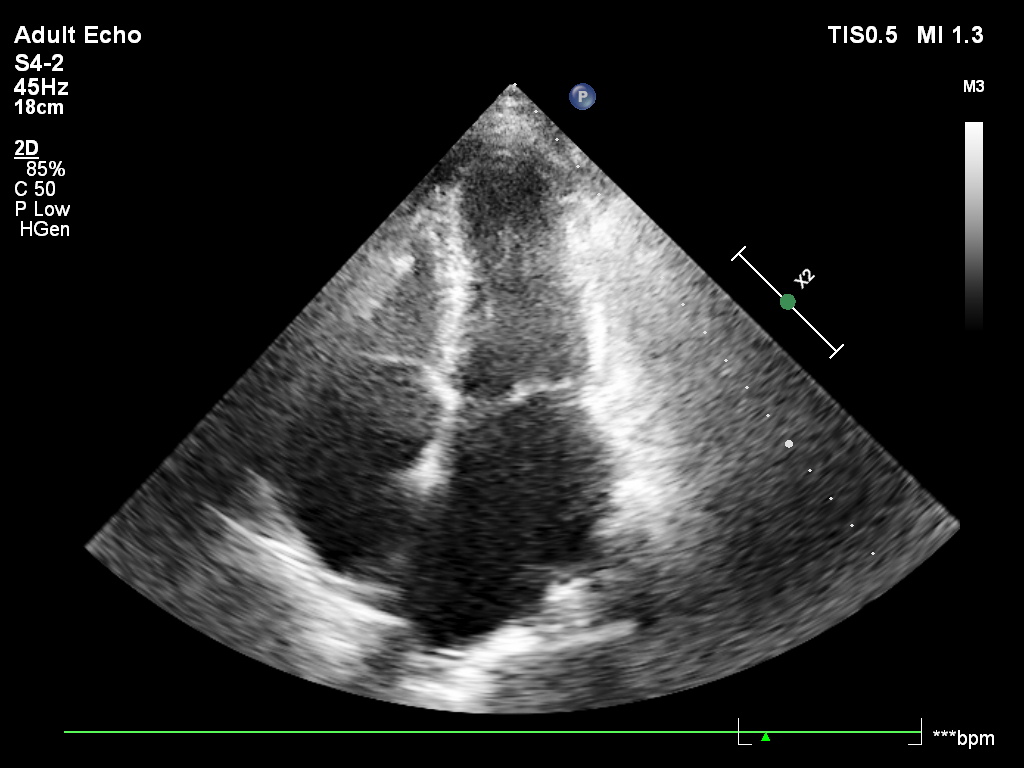

Pacjent , lat 66, przyjęty z podejrzeniem sepsy, w badaniu echokardiograficznym ujawniono duże, ruchome wegetacje na trzech zastawkach – mitralnej, trójdzielnej i płucnej . Wegetacje najlepiej widoczne były w projekcjach podmostkowych . Obraz jest dramatyczny: wysokie ryzyko powikłań zatorowych i przeciążenia prawego serca.

A 66-year-old patient admitted with suspected sepsis underwent echocardiography, revealing large, mobile vegetations on the mitral ,tricuspid and pulmonary valves .Vegetations were most clearly visualized in subcostal projections. The findings are dramatic, indicating a high risk of embolic complications and right heart overload.

w projekcji – podmostkowej 4 jamowej uwidoczniono wegetacje na zastawce trójdzielnej i mitralnej

projekcja podmostkowa 4 jamowa- umiarkowana niedomykalność trójdzielna